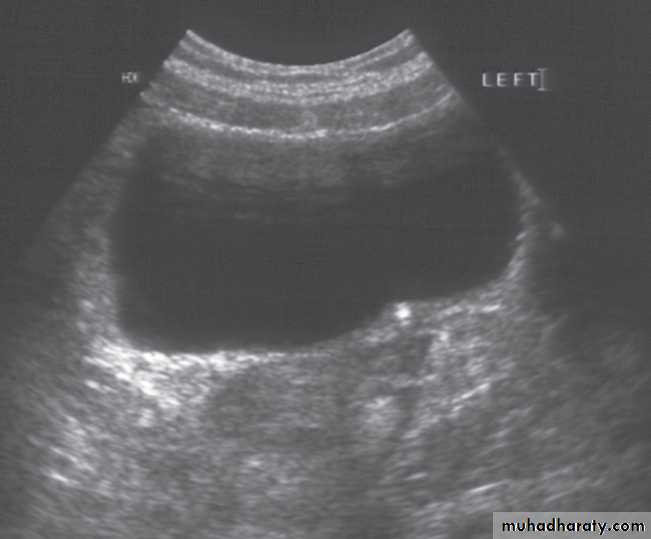

Ultrasound Dilatation of the pelvicaliceal system ( hydronephrosis ) is demonstrated sonographically as a multiloculate fluid collection in the central echo complex, caused by pooling of urine within the distended pelvis and calices .

Major DDX are multiple renal cysts. With prolonged obstruction, thinning of the cortex due to atrophy will be seen.